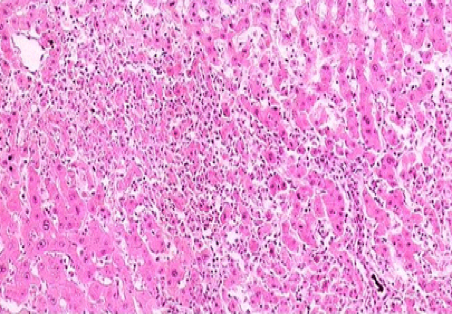

镜下见广泛的肝细胞变性,以胞浆疏松化和气球样变最为普遍。肝小叶内可有散在的点状坏死。嗜酸性小体并不常见。由于肝细胞索网状纤维支架没有塌陷,故再生的肝细胞可完全恢复原来的结构和功能。门管区及肝小叶内有少量炎细胞浸润。黄疸型者坏死灶稍多、稍重,毛细胆管管腔中有胆栓形成。

(1)轻度慢性肝炎:肝细胞变性,点灶状坏死或凋亡小体,偶见轻度碎片状坏死,门管区周围纤维增生,肝小叶结构完整。

(2)中度慢性肝炎:肝细胞坏死明显,有中度碎片状坏死和特征性的桥接坏死。小叶内有纤维间隔形成,但小叶结构大部分保存。